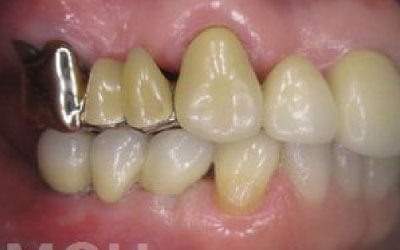

インプラントだと固定式なので取り外す必要もなく煩わしさが圧倒的に少ないです。見た目も、他の人からはわからないケースがほとんどです。

入れ歯の様に取り外す必要がなく、ご自身の歯の様な感じで噛めるところがメリットです。

そして一番のメリットは、周囲の歯の寿命を短くさせないことです。